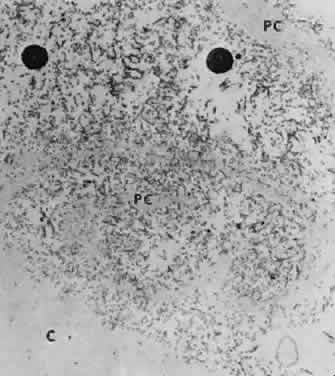

Accumulation of exfoliative material may be detected histopathologically throughout the anterior segment to include the lens, iris, trabecular structures, conjunctiva, ciliary body, and zonules. The deposition of fibrillar eosinophilic material on the anterior lens capsule is the classic histopathologic feature of XFS (Fig. 9). Ultrastructural studies also indicate some degree of actual exfoliative changes or peeling of the anterior lens capsule74 (Figs. 10 and 11). In addition, Ashton and associates describe a degenerative band containing exfoliative material within the inner half of the lens capsule.5 Bertelsen and coworkers independently noted projection of coarse fibrils from the lens surface into the deep portion of the lens capsule to form an amorphous layer of the lens capsule between the lens epithelium and normal lens capsule.6 Thus, studies indicate that exfoliative material accumulates on the anterior lens surface but also that the lens capsule itself may be involved, and that the underlying epithelial layer may at least partially contribute to the production of the exfoliative material.

Exfoliative material consists of an irregular meshwork of fibers composed of fibrillar subunits.74,92 Masses of these fibers correspond to the material seen clinically (see Fig. 10). The individual fibrils, which measure 6 to 8 nm in diameter and exhibit cross-banding at 10- to 12-nm intervals, are hypothesized to consist of macromolecules with a protein backbone and polysaccharide side chains.93–95 In contrast to collagen, the amino acid content of exfoliative material lacks hydroxyproline.96 Ringvold and Husby noted histochemical, immunologic, and ultrastructural features that led them to classify exfoliative material as an amyloid-like substance.97 Repo and associates note Congo red-positive staining for amyloid in the vessel walls of 7 of 13 iris specimens from exfoliation patients and believe that these findings support the theory that XFS is associated with amyloid.59 Immunohistochemical studies by other investigators show heparin sulfate and chondroitin sulfate proteoglycans, laminin, entactin/nidogen, fibronectin, and amyloid P protein to be components of exfoliation material.98,99 Schlötzer-Schrehardt and coworkers suggest that the material may be an expression of a disordered extracellular matrix synthesis.98